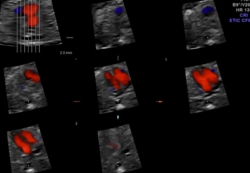

従来のスキャンに加え、3D表示する事が可能になり、更には時間軸上で連続的に3D表示する4Dの域にまで達しています。

更に近年では画像処理技術の向上により、より詳細且つリアルに表示する事が可能となりました。

4D超音波画像診断装置の普及実現したことで、「我が子の姿を少しでも早くリアルに見たい」「胎児の成長を実感したい」という妊婦のニーズに幅広く応えるほか、胎児疾患の早期発見・早期治療に進展に大きく寄与することが期待されています。

STIC機能は,Volumeデータから心拍数を推定し1心拍分の動画像を再構築し,直交三断面やレンダリング画像を表示します。任意断面の観察,解析,計測等が可能であり、胎児心エコー検査を強力にサポートします。